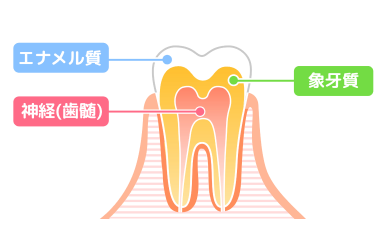

歯の構造

エナメル質

- 歯の表面

- 体の中で最も硬く水晶と同じ硬さ

- 酸に弱い

象牙質

- エナメル質の内側にある部分

- エナメル質より柔らかい

- 酸に弱い

神経(歯髄)